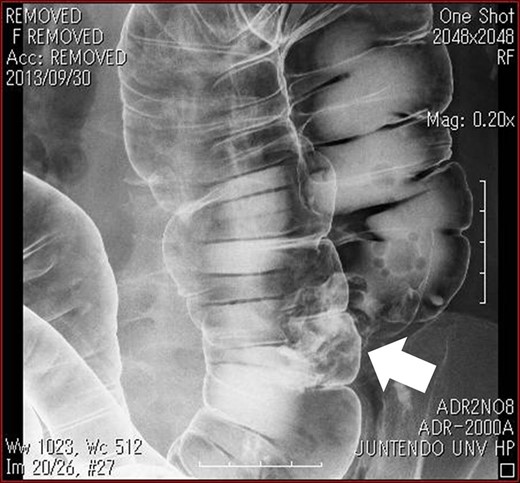

Barium enema revealed an elevated lesion in the ascending colon (arrow).